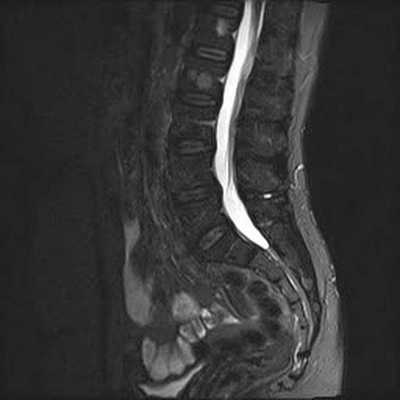

Снимок МРТ поясничного отдела позвоночника в сагиттальной проекции при остеохондрозе

МРТ поясничной области - современный метод диагностики патологических процессов, ограничивающих функциональность нижних отделов позвоночника. Магнитно-резонансная томография проходит без хирургических манипуляций, процедура безболезненна и безопасна для пациента. Метод визуализирует расположение костных элементов, хрящей, состояние мягких тканей, невральных структур и кровеносных сосудов.